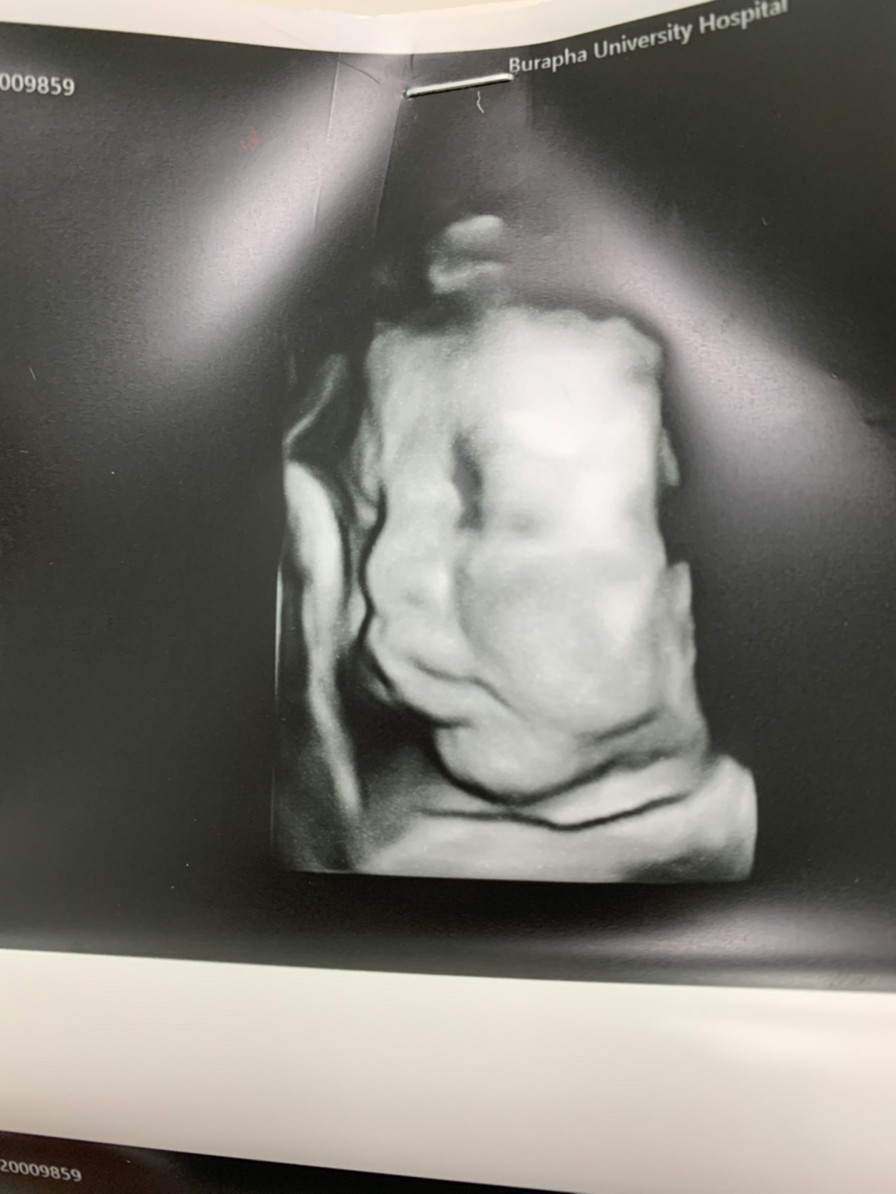

ลูกสาวค่า

น้องเอิร์ท'น้องมาส